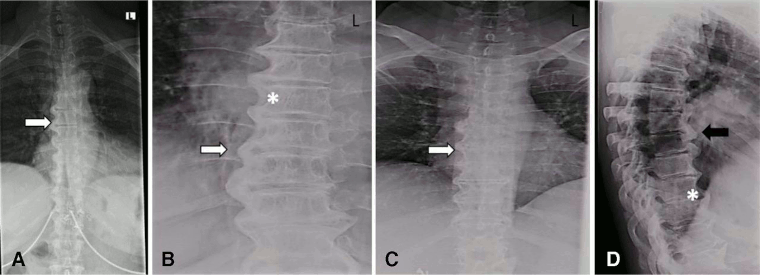

X-ray images of the thoracic spine of a patient with DISH. (A–C) Posterior–anterior and (D) lateral: large right-sided flowing bridges (white arrows). Note the space between the ligament and the vertebral body (*). Thick flowing ossification of the anterior lateral ligament is shown (black arrow)

Mader R, et al. RMD Open 2020; 6: e001151. doi: 10.1136; used with permission